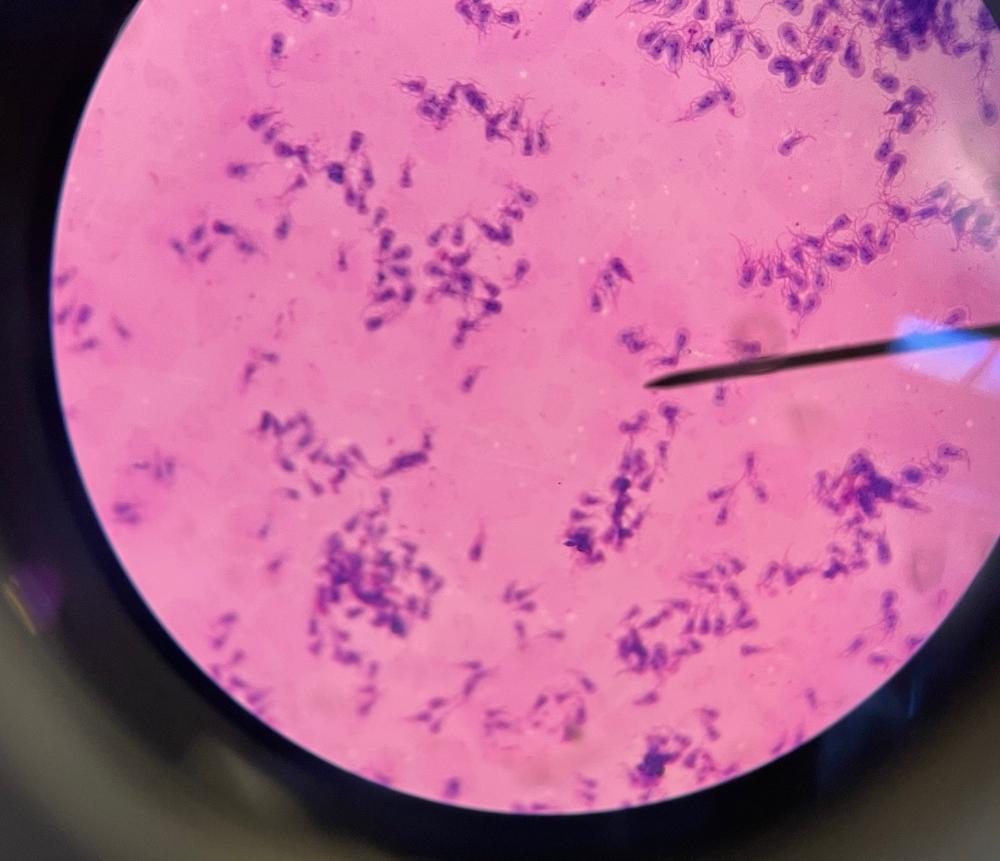

Giardia trophozoites

Necator larvae

Strongyloides larvae